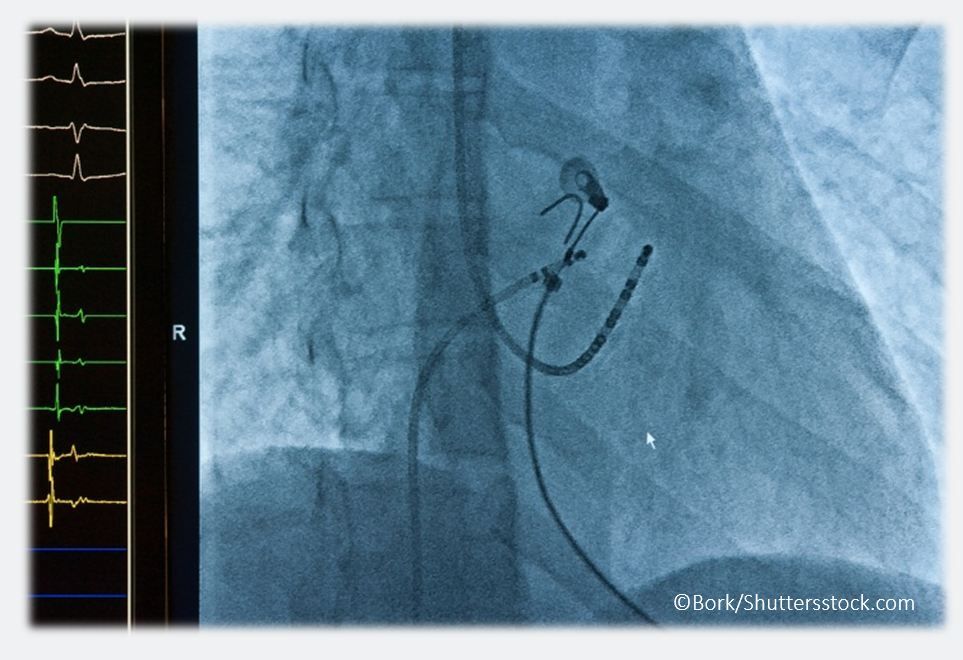

One of the most long-awaited trials in cardiology, the atrial fibrillation CABANA1 trial made its debut at the Heart Rhythm Society meeting (May 9-12) in Boston earlier this year. The trial has generated almost as much discussion as the sham-controlled ORBITA trial did at the American College of Cardiology meeting, ie, some are calling CABANA a “game-changer” while others say the results won't impact their practice.

CABANA1 (Catheter Ablation versus Antiarrhythmic Drug Therapy for Atrial Fibrillation Trial) asked whether percutaneous catheter ablation therapy for eliminating AF was superior to pharmacologic therapy (with either rate or rhythm control). Option A is the question posed by a recent trial published in JAMA2 that showed that surgical ligation of the LAA at the time of concurrent cardiac surgery reduced the risk of stroke and all-cause mortality. Option B reflects the AFFIRM trial,3 which concluded that management of atrial fibrillation with the rhythm-control strategy was equivalent to the rate-control strategy, with potential for fewer adverse drug side effects. Option D is the question at the center of the RACE-2 trial,4 which concluded that in patients with permanent atrial fibrillation, lenient rate control is as effective as strict rate control and is easier to achieve.

One thing is certain, though … the cardiology/electrophysiology community is increasingly embracing ablation as an emerging therapy for atrial fibrillation. The procedure, based on this randomized, first-of-its-kind trial, appears to be a safe alternative for AF patients and to be at least equivalent to and in some selected patients, superior, to pharmacologic therapy.